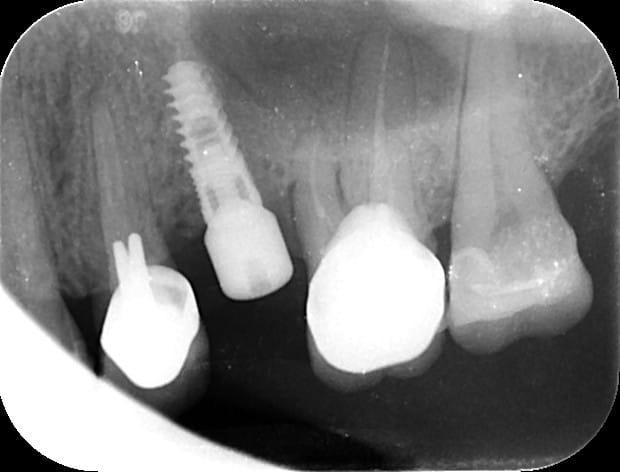

pour ceux qui m'ont demandé les images...;-)

la reconstruction 3D du scan

la planif avec le recalage du scan

la même en vue latérale avec le mapping osseux (mais qui devait merder, à cause de l'alim qui était en train de lâcher...)

et la radio post op...

et pour le fun, ce que j'ai fait ce matin en 15min là aussi...

la patiente ne voulais pas faire de sinus lift car elle avait eu pas mal de pb de ce côté là...

donc, j'ai posé l'implant à raz le long du plancher sinusien

et bien, je souhaite bien du plaisir à qui doit poser un implant de la sorte à main levée en prenant à la fois en compte le sinus et l'émergence du col de l'implant pour ne pas avoir de pb pour faire la prothèse...

à part y aller millimètre par millimètre et prendre des radios à chaque fois....

P.S: j'ai quand même vérifié après l'insertion finale que je pouvais connecter un transfert...bilan, aucun problème!

Capture1 bzketg - Eugenol

Sinus zbjhxn - Eugenol

votre système est peut être bien mais ne croyez pas que sans on ne peut rien faire...

d'autant plus que sur une coupe, l'axe n'est pas génial par rapport à la 6....

2 coupes scan pour exemple, de ce que n'importe quel praticien lambda, peut faire à main levé avec un minimum de sensibilité et d'attention. implant posé et l'autre coté va être fait pareil

P.S: pour goupil, oui la 16 n'est pas dans une forme olympique...on peut en dire autant pour la 14...

seulement voilà: ce cas m'est adressé, j'ai longuement parlé avec mon confrère et la patiente des différentes options et c'est celle qui a été retenue...

pour info quand même, ces dents sont totalement asymptomatiques et n'ont aucune mobilité...